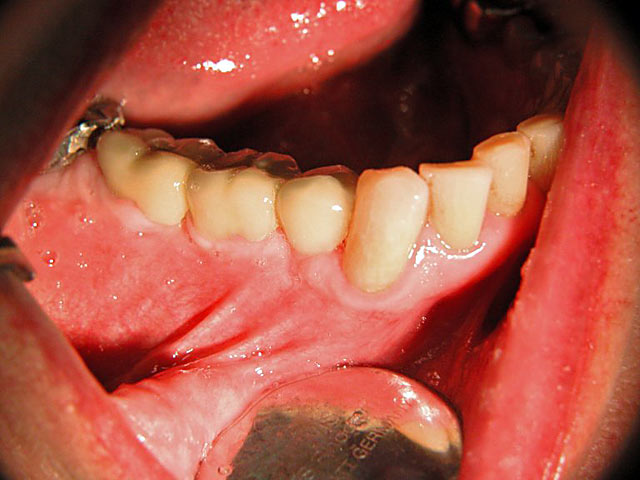

Die folgenden Patientenfälle sollen Ihnen einen Einblick in die Möglichkeiten der modernen Implantation geben.